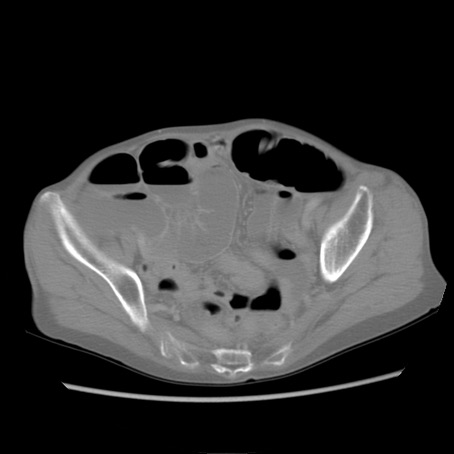

冠状断像